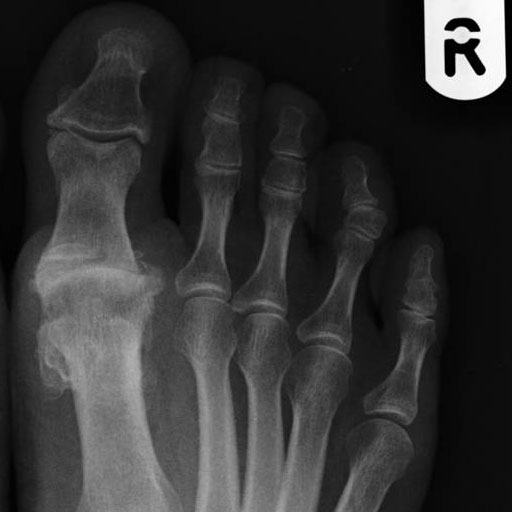

Big toe arthritis

1st Metatarsophalangeal (MTP) joint arthritis

Wear and tear at the joint of the midfoot and the great (big) toe cause loss of cartilage and the smooth movement of the joint. As the smooth joint surface is lost this becomes painful and movement restricted.